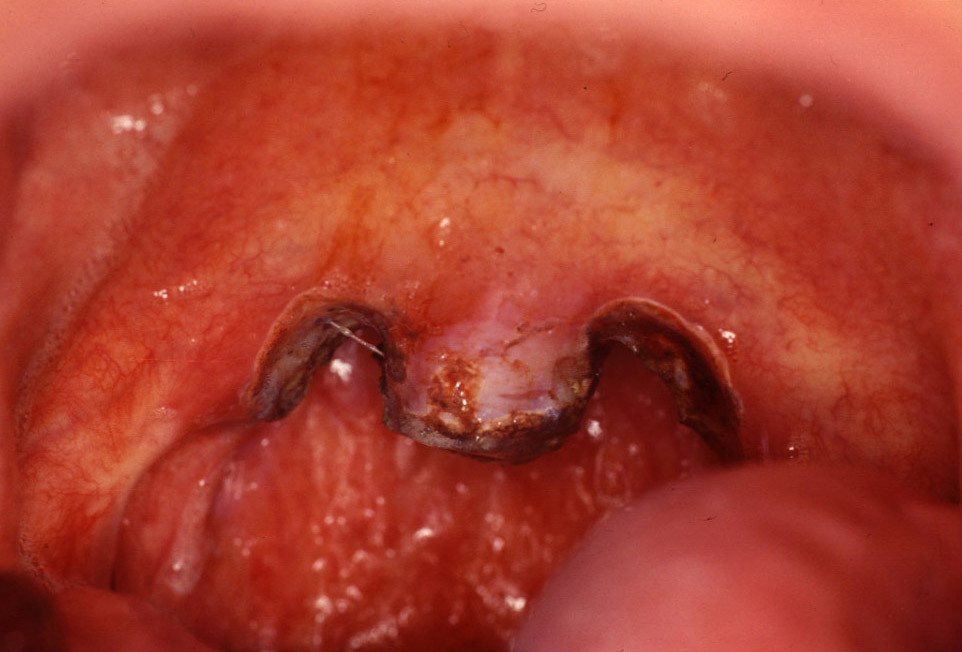

View of the soft palate shows the typical laser incisions to treat chronic snoring.